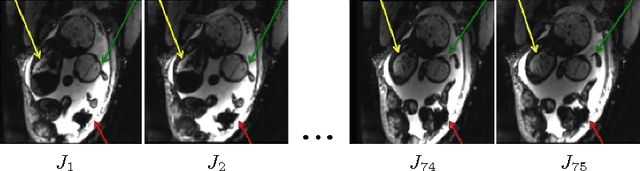

Abstract:We present a robust method to correct for motion in volumetric in-utero MRI time series. Time-course analysis for in-utero volumetric MRI time series often suffers from substantial and unpredictable fetal motion. Registration provides voxel correspondences between images and is commonly employed for motion correction. Current registration methods often fail when aligning images that are substantially different from a template (reference image). To achieve accurate and robust alignment, we make a Markov assumption on the nature of motion and take advantage of the temporal smoothness in the image data. Forward message passing in the corresponding hidden Markov model (HMM) yields an estimation algorithm that only has to account for relatively small motion between consecutive frames. We evaluate the utility of the temporal model in the context of in-utero MRI time series alignment by examining the accuracy of propagated segmentation label maps. Our results suggest that the proposed model captures accurately the temporal dynamics of transformations in in-utero MRI time series.

Abstract:We present a robust method to correct for motion and deformations for in-utero volumetric MRI time series. Spatio-temporal analysis of dynamic MRI requires robust alignment across time in the presence of substantial and unpredictable motion. We make a Markov assumption on the nature of deformations to take advantage of the temporal structure in the image data. Forward message passing in the corresponding hidden Markov model (HMM) yields an estimation algorithm that only has to account for relatively small motion between consecutive frames. We demonstrate the utility of the temporal model by showing that its use improves the accuracy of the segmentation propagation through temporal registration. Our results suggest that the proposed model captures accurately the temporal dynamics of deformations in in-utero MRI time series.